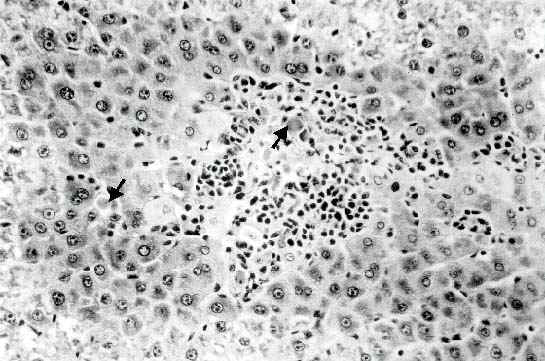

Effect of Ochratoxin A on Liver Tissue. We did a preliminary experiment to study the effect of OTA administration on liver apoptosis at different days after toxin administration in order to identify the most suitable time for the occurrence of apoptotic bodies. Examination of the liver after mice administered a dose of 1.8 mg OTA/kg body weight twice a week for two weeks, disclosed the presence of a difference between hepatocytes of different zones of the acinus, in that an eosinophilic-dense cytoplasm was characteristic of the liver cells located in the periphery of the acinus. Apoptotic bodies were frequently observed in the proximity of the centrilobular vein and in the periphery of the acinus (Figure 1)

Figure 1: Liver of mouse given 1.8 mg/kg body weight of OTA twice a week for one week. Many apoptotic bodies are present either in clusters in the central area (arrows) or scattered between the surrounding hepatocytes with condensed cytoplasm (Original magnification: x 300)

They were scattered or in small clusters, and as for their localization they were either in the extracellular space or inside the cytoplasm of intact hepatocyte cell. Only little evidence of inflammatory reaction could be observed at one week, no signs of lytic cell necrosis could be detected. At two weeks, an increase in the number of acidophilic globules was observed, they were often found surrounded by mononuclear cells (Figure 2).